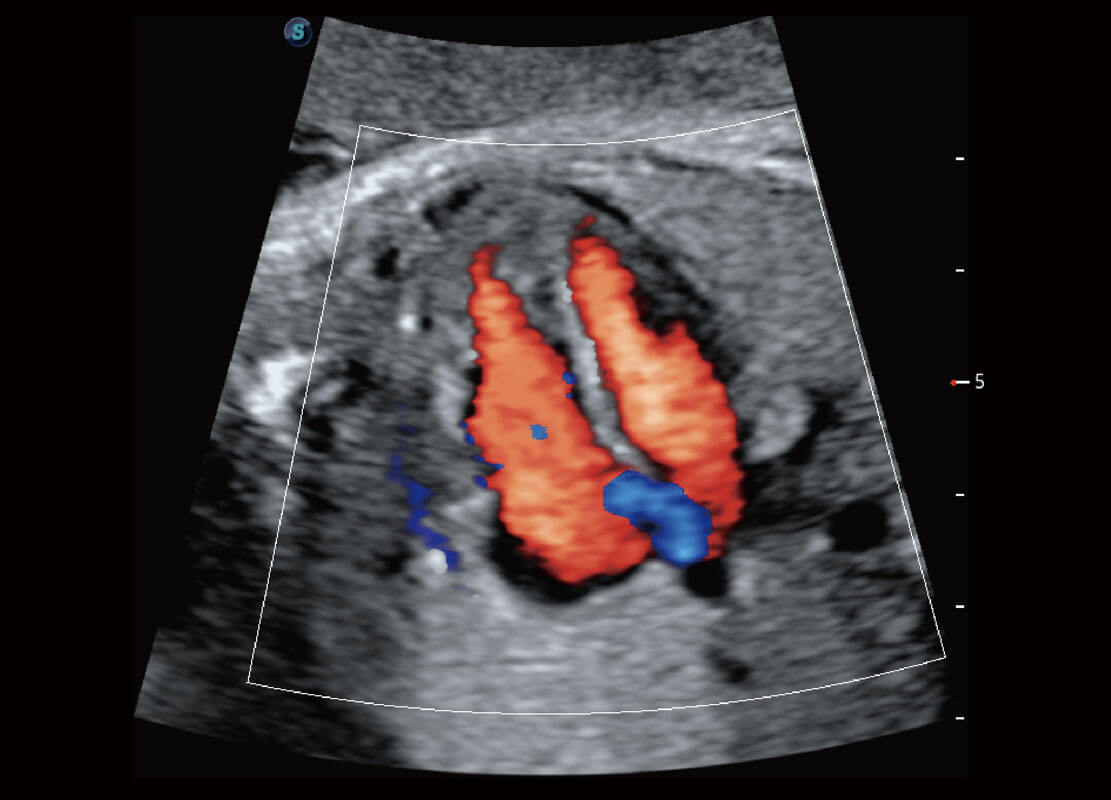

盆底超声

P60为盆底超声检查提供应用方案,多种腔内及腹部容积探头提供从二维、三维到四维的优异图像品质,实时快速三维容积数据获取,专业的测量工具包等人性化设计,为超声医生诊断提供有力保障。

Lev.Hiat A-r: 16.33 cm2

Lev.Hiat H-r: 53.70 mm

Lev.Hiat W-r: 43.96 mm

Lt-LUG-r: 24.16 mm

Rt-LUG-r: 19.94 mm

S-Pelvic

能够简化盆底检查的操作流程,可在二维模式及三维成像模式下实现一键自动提取出标准切面、自动识别当前切面、自动测量,提升盆底检查的高效性,同时也能让青年医生快捷的获得准确的检查结果。